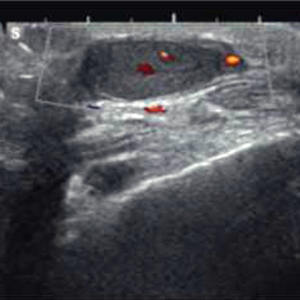

Noviembre 2025. Hospital Italiano

Masculino de 61 años. Masa dolorosa en cara anterior de pie derecho.